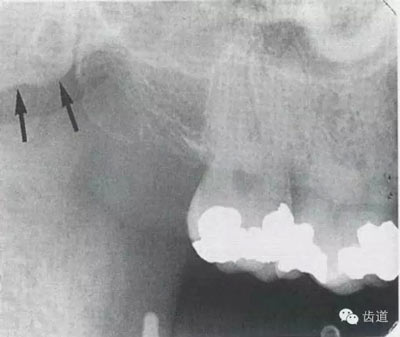

在最后一個(gè)磨牙遠(yuǎn)中區(qū)域,其邊緣向后上,X線片上常呈稀疏的網(wǎng)狀結(jié)構(gòu),為正常疏松區(qū)。

在上頜結(jié)節(jié)后方,呈長(zhǎng)條狀邊緣整齊、寬約0.2cm、長(zhǎng)約1cm、直的或下端略向后方彎曲的密度稍高的影像。